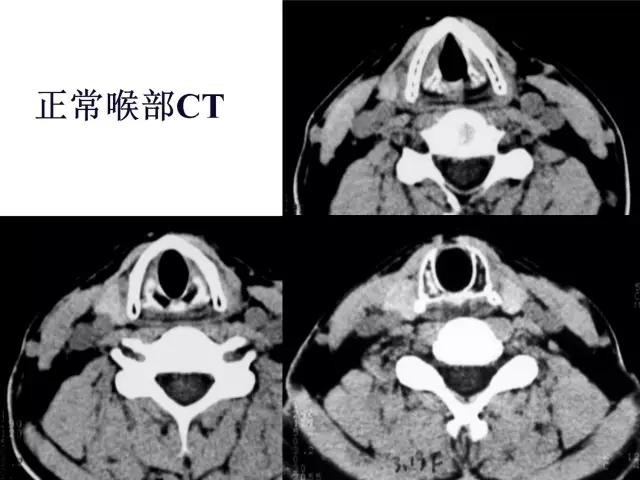

正常喉部CT

7、喉腔:

- 声门上区:声带之上,室带以上喉腔称为喉前庭。声带与室带之间的腔隙为喉室。室带(假声带),由室韧带、肌纤维及粘膜组成,前端起于甲状软骨前角的上中段内面,后端止于杓状软骨前上面。

- 声门区由声带构成,喉室下方由声韧带、肌纤维和粘膜构成,前端起于甲状软骨前角中段内面,后附着于杓状软骨声带突,厚约5mm。张开时出现一个等腰三角形裂隙称声门裂,发音时声带内收。

- 声门下区为声带下至环状软骨下缘以上的喉腔,正常气道与环状软骨间粘膜厚度不超过1mm。

2、CT、MRI检查